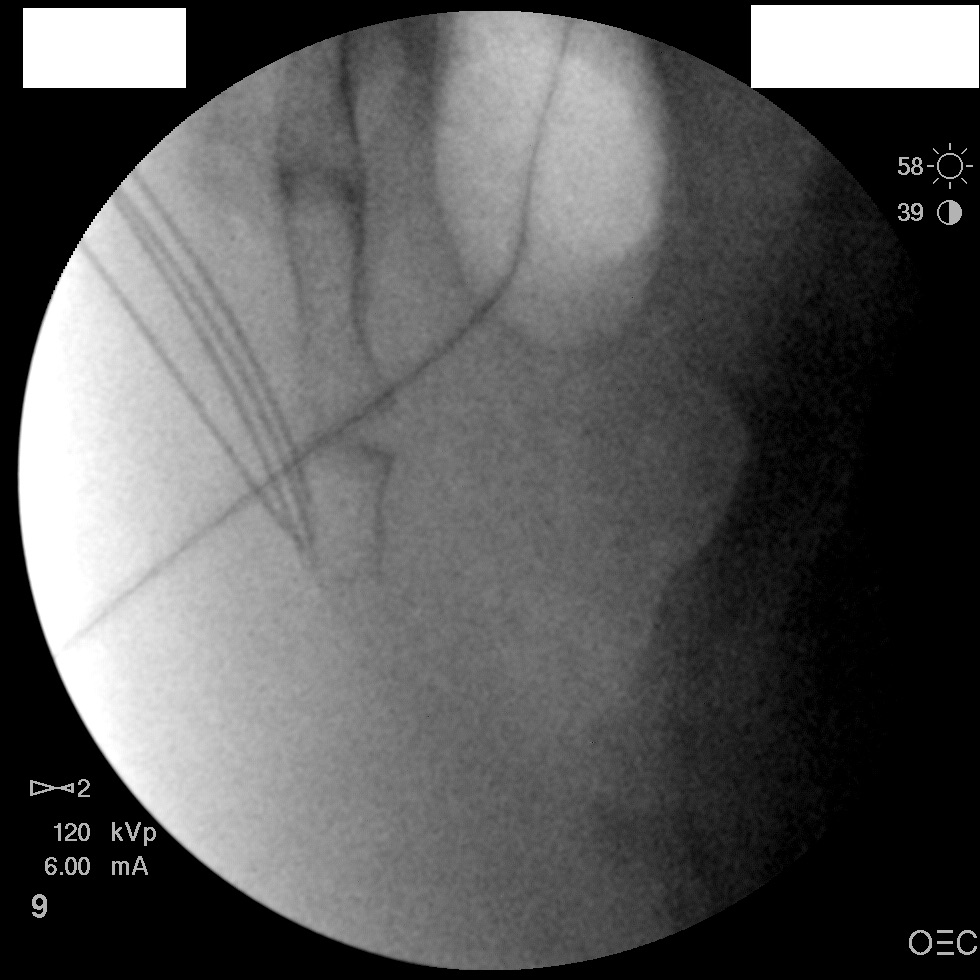

I have a patient with several months of coccyx pain. Worse with sitting, TTP over coccyx. Otherwise normal exam. No trauma, but she has an anteriorly displaced coccyx. Failed NSAIDs and no one around me does good pelvic floor PT. I scheduled her for ganglion impar injection, but her insurance won't pay for it. They wouldn't even let me to a peer-to-peer... they just straight up said they won't cover it. Any other treatment options? I don't want to send her to a surgeon. Thanks.